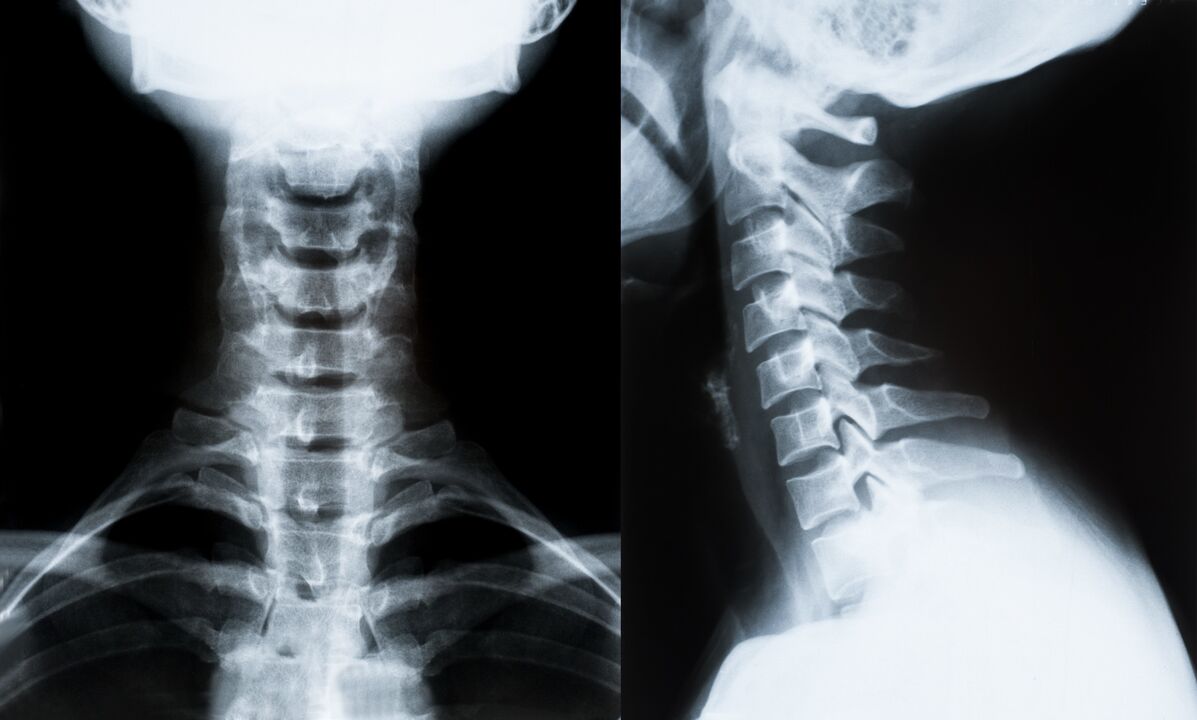

Основните методи за диагностика и по-нататъшно определяне на лечението на остеохондрозата на цервикалния гръбначен стълб:

- рентгенова снимка. Най-малко ефективният, но традиционен диагностичен метод.

- Ядрено-магнитен резонанс е най-ефективният диагностичен метод. При този вид изследване на пациента се виждат всички необходими структури.

- При необходимост от измерване на промените се използва компютърна томография. Установява наличието на херния и други неща.

- Последният метод е ултразвуково дуплексно сканиране. Този метод на изследване определя скоростта на кръвния поток в артериите.

Невъзможно е точно да се определи заболяването на гръбначния стълб у дома.